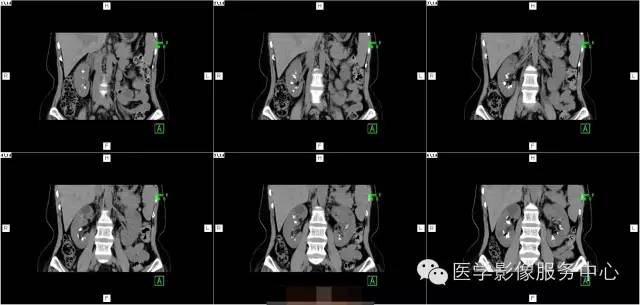

病史:

女,37岁,血尿一周

髓质海绵肾(简称MSK)又称Cacchi Ricci disease,是一种先天发育性肾髓质囊性病变,发生率约1:2000-5000,多见于40-60岁男年,70%为双侧肾脏发病,病变局限于髓质范围内,常累及两侧肾的多数锥体和乳头,形成许多数毫米的囊腔使髓质如海绵状,故名海绵肾,病理特点为集合管远端扩张,形成圆形或不规则型囊腔,囊内壁衬以立方或扁平上皮,囊内充溢脱离的上皮及钙化形成的小结石。

临床表现:

1、多数患者无症状,实验室检查正常。

2、若并发感染、结石可出现血尿,绞疼,尿路刺激征。

1、腹部平片表现肾影正常或稍增大,两侧或单侧肾实质内多发圆形、类圆形或不规则形结石,直径2-5MM,呈簇状或扇形分布,有时平片可表现阴性。

2、静脉肾盂造影表现肾脏大小正常或轻度增大,造影剂在肾乳头或扩张集合管呈放射条纹状、花束状,肾功能一般正常。

3、CT平扫表现一个或多个肾锥体内散在或蔟团状多发结石,呈花瓣样或扇形分布;部分腹部平片阴性,CT平扫可发现肾锥体内细小的结石。增强扫描表现扩张的肾集合管内有条纹状、刷状、小囊状或扇形的造影剂浓聚。部分患者肾实质内可见多发小囊肿。